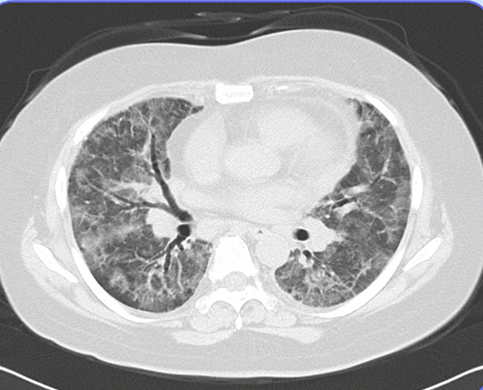

関節リウマチ(RA)の診療において、間質性肺炎(ILD)の合併は予後を左右する極めて重要な因子です。RA患者さんは肺病変を合併する頻度が高いため、治療開始前には…